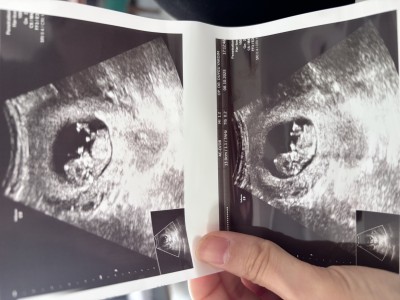

Kızlar nasıl neye göre tahmin yapılıyor hiç anlamıyorum cidden ama yinede sormak istedim bi bakar mısınız tahminleriniz neler

Merhaba benimde böyleydi. Benim oğlum oluyo tahminimce sizin de erkek. Belli olunca yazın siz de 🥰

Alttaki resimde hafif çıkıntı var , yani bn ôyle görüyorum , Rabbim gönlüne göre versin inşallah canım 🤲🏻